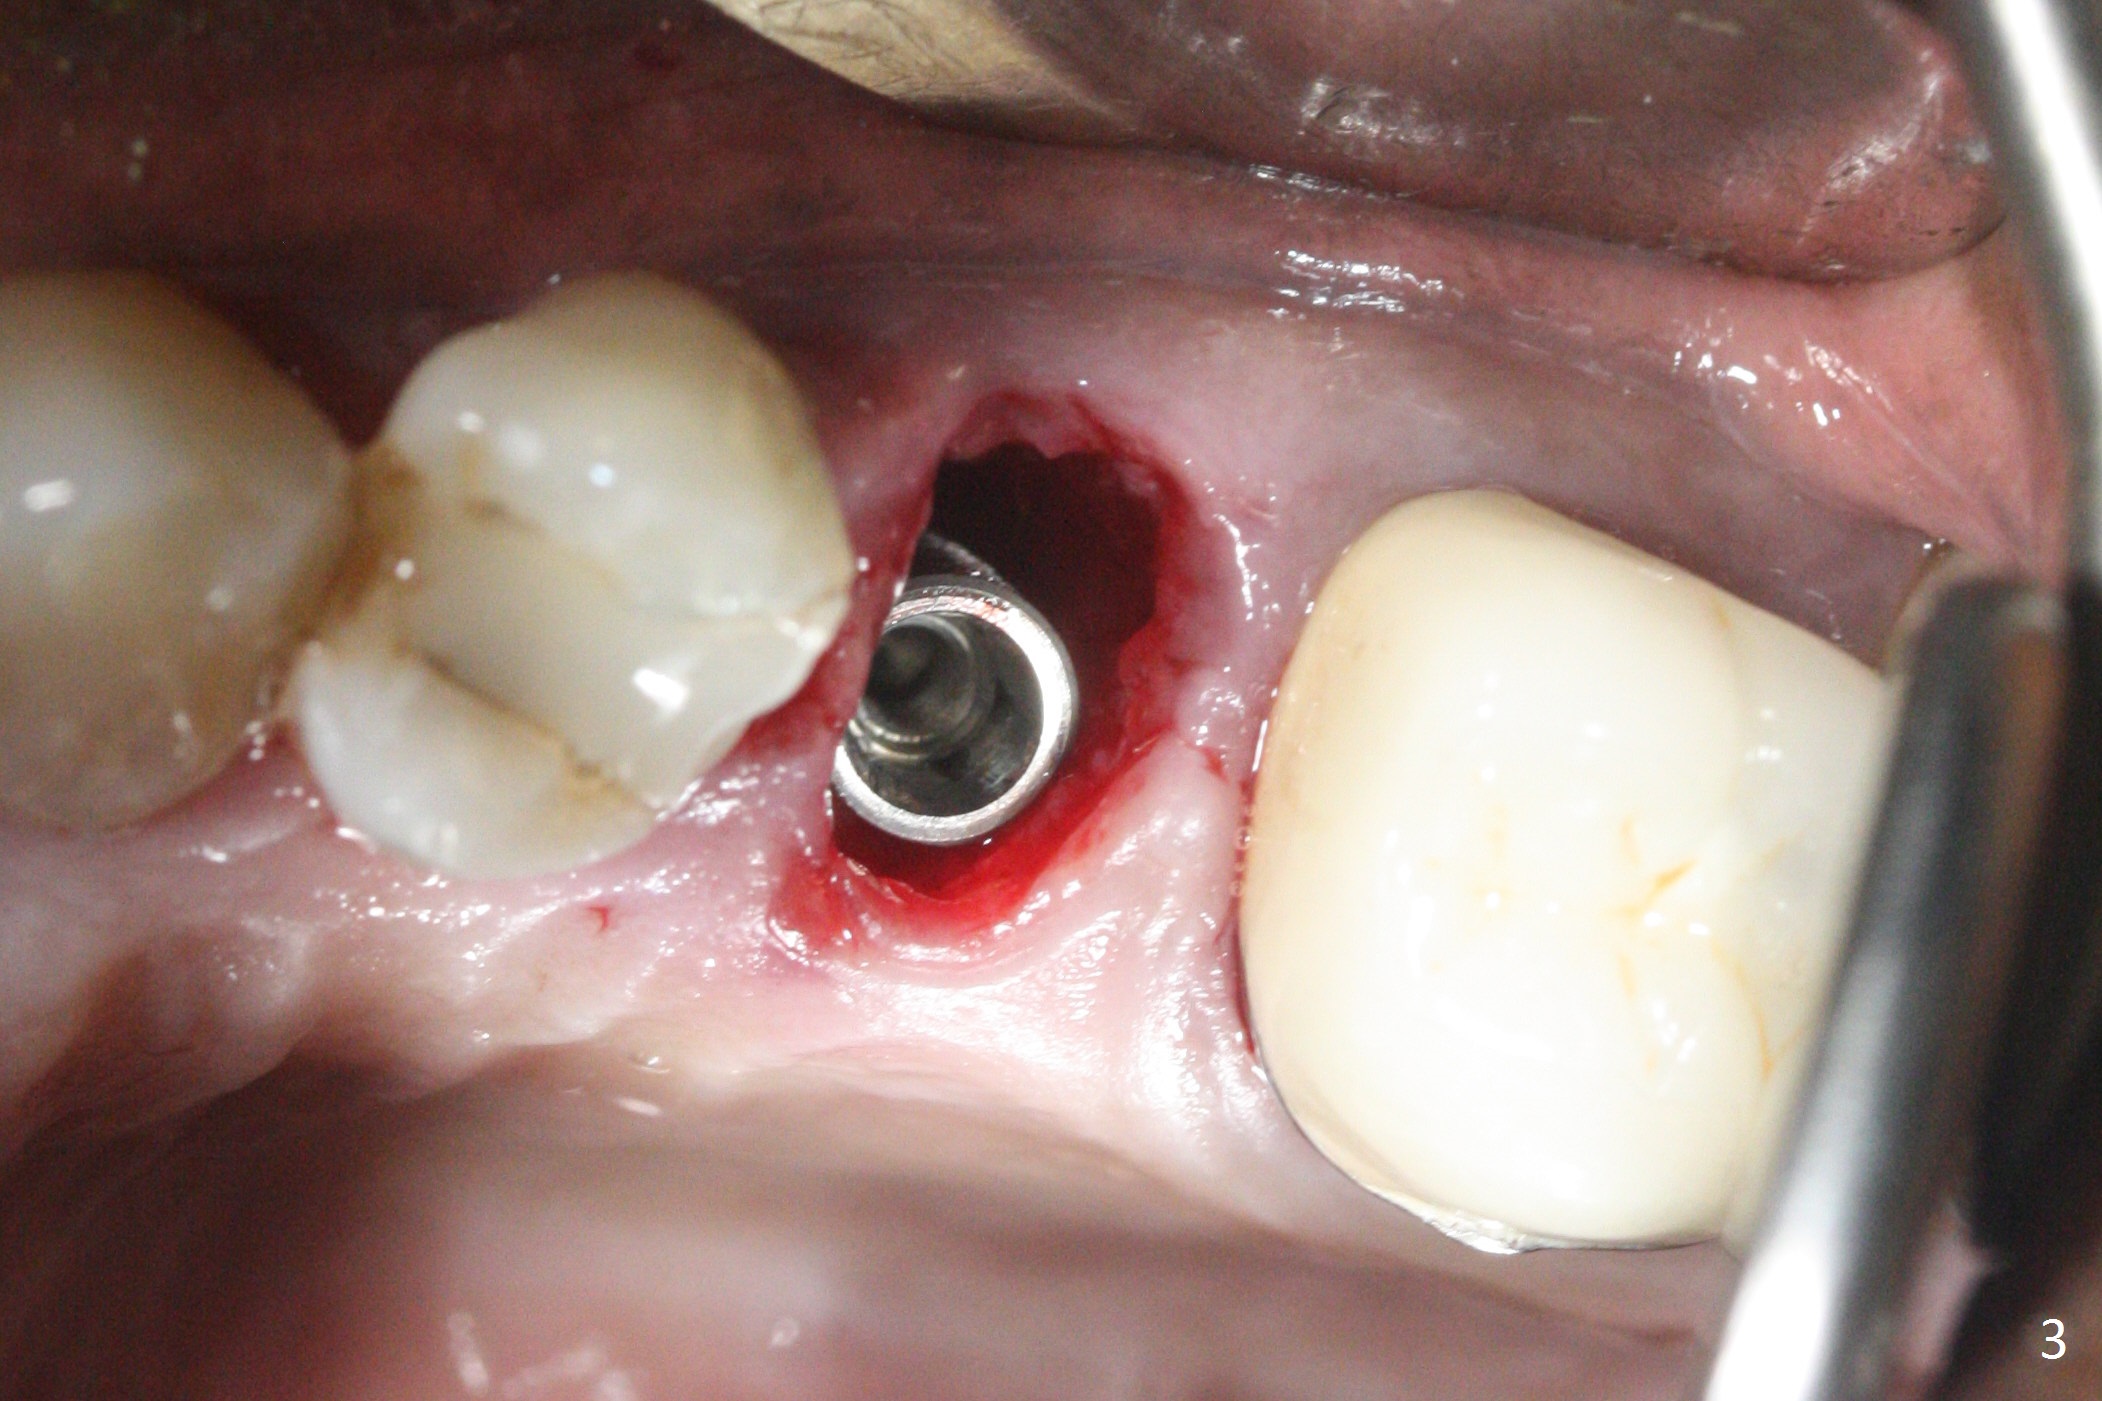

Since the apical native bone is limited at #13 after extraction, no PA is taken until a 4x11 mm dummy implant is placed after 1.6 mm and 3.3 mm drills for 13 mm (Fig.1). After using Lindamann bur to move the osteotomy distal and reusing 3.3 mm drill, the trajectory of a 4.5x11 mm IBS dummy implant improves (Fig.2,3 with low stability). When the implant is removed, the buccal portion of the socket is found to be perforated (Fig.4 P). Although the reason for the perforation is unknown, it is repaired by insertion of a piece of PRF plug, followed by allograft. #1 and 2 in Fig.4 represent the 1st and 2nd osteotomies, as shown in Fig.1 and 2, respectively. The trajectory of the final 5x13 mm implant is acceptable (Fig.5-7, different angulations), so is insertion torque (45 Ncm). After placing a 5.5x4(4) mm abutment, an immediate provisional is fabricated (Fig.8 P) with occlusal clearance (*). The interdental papillae remain in place 12 days postop (Fig.9 *). There is no sign of postop sinus infection. The provisional is loose 18 days postop; the abutment is changed to 5x4(3) mm (Fig.10). It is difficult to catch the mesial margin of the abutment for impression 4 months postop, due to poor oral hygiene and the short cuff (3 mm, Fig.11). The appointment for impression is rescheduled with emphasis on oral hygiene and no wearing the provisional for a few days prior to next appointment. Bone has grown into the space between the 1st and 2nd threads 5 months post cementation (Fig.12) and the bone is normal, solid and dense 2 years 11 months post cementation (Fig.13 >). There is mesial open margin of the tooth #14 (Fig.13,14 *).